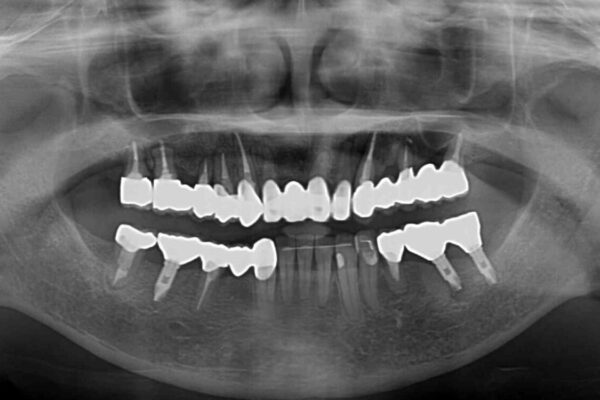

治療後

• 放置したインプラントとインビザライン 全顎リカバリー治療 治療後画像